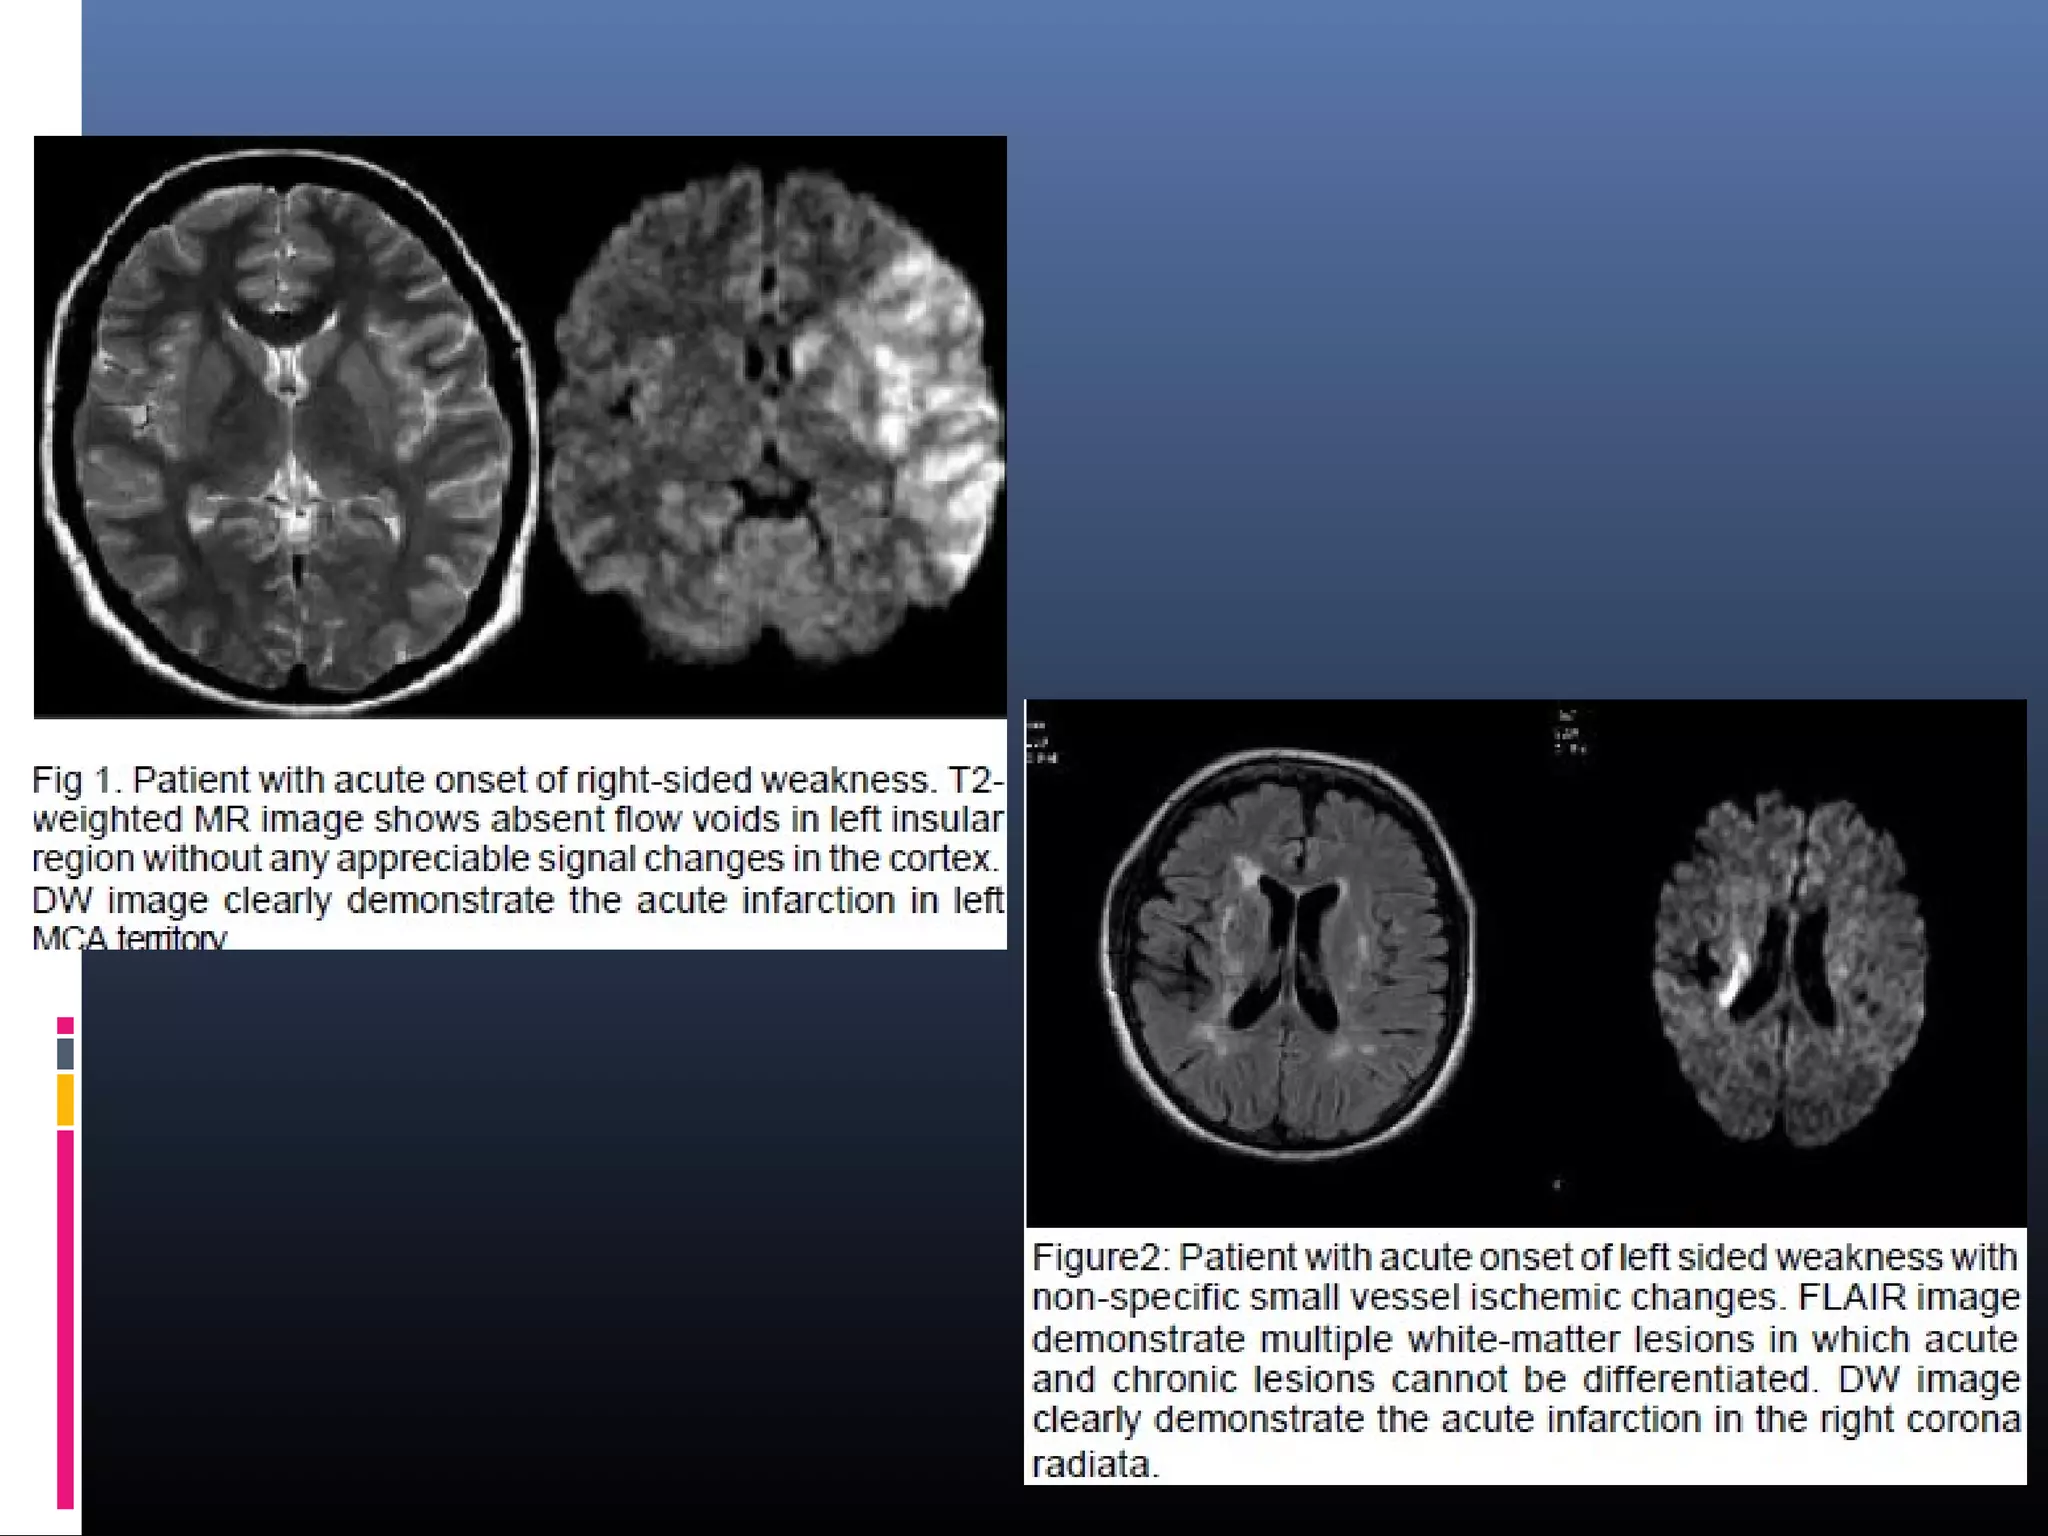

Evaluation of acute stroke on DWI

 The DWI and ADC maps show changes in ischemic brain within

minutes to few hours

 The signal intensity of acute stroke on DW images increase

during the first week after symptom onset and decrease

thereafter, but signal remains hyper intense for a long period

(up to 72 days in the study by Lausberg et al)

 The ADC values decline rapidly after the onset of ischemia and

subsequently increase from dark to bright 7-10 days later .

 This property may be used to differentiate the lesion older than

10 days from more acute ones (Fig 2).

 Chronic infarcts are characterized by elevated diffusion and

appear hypo, iso or hyper intense on DW images and

hyperintense on ADC maps